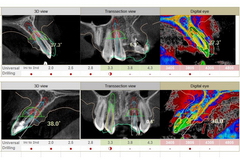

診査診断が極めて重要です。

インプラントの位置や角度、深さなどを決定します。

インプラント埋入&仮歯装着

デジタル診断によって作成したサージカルガイドを使用します

柱と仮歯が固定されています